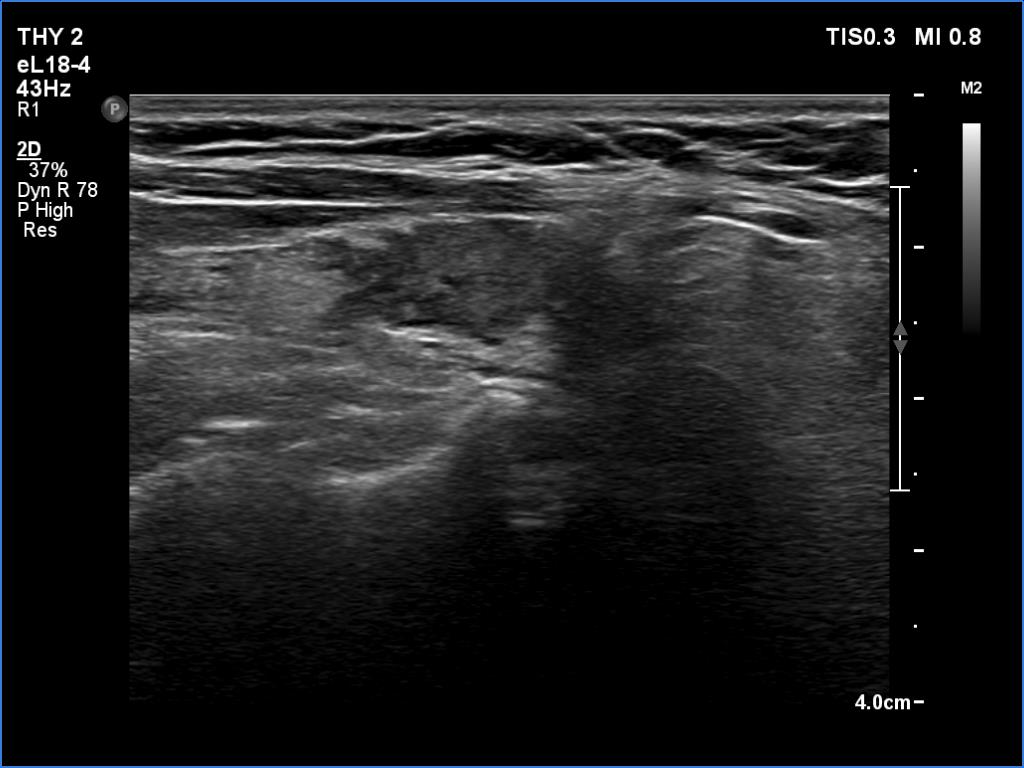

Clinical data: A 64-year-old woman came to a routine follow-up. She has been operated on a multinodular goiter for more than 20 years. A total thyroidectomy was performed. A recent thyroid ultrasound resulted in thyroiditis or recurrent nodule.

Ultrasonography. Great part of the lobes was composed of hypoechoic mass which showed irregular shape.

Overwhelming majority of the operated thyroids became hypoechoic.

This is one of the characteristic presentations of an operated thyroid, a lobe is partly hypoechoic partly echonormal.